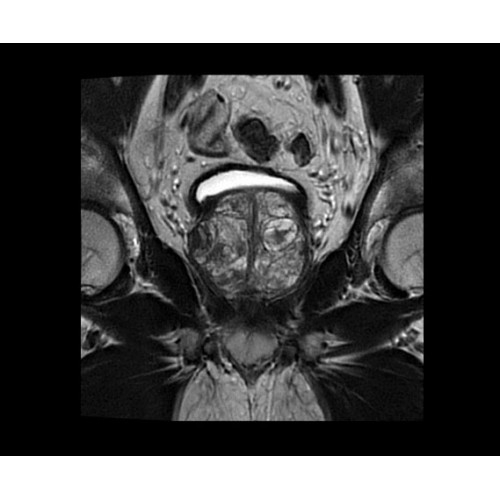

SIGNA PET/MR 3.0T — это гибридная система, в которой совмещаются две принципиально разные технологии — магнитно-резонансную томографию (МРТ) и позитронно-эмиссионную томографию (ПЭТ). Система отличающийся высокой чувствительностью и эффективностью и предназначена для диагностики в области онкологии, неврологии, кардио-васкулярных исследований, исследований воспалительных процессов.

Компания GE Healthcare представляет революционную, полностью интегрированную систему SIGNA PET/MR1, в которой сочетаются времяпролетная технология (TOF) и возможности напряженности магнитного поля 3.0 Тл. Мы поможем вам поднять исследования на более высокий уровень. SIGNA PET/MR позволяет достичь впечатляющей точности и скорости исследований, а благодаря новейшей технологии реконструкции Q.Clear2 качество изображений улучшается в два раза. Кроме того, в систему включен полный набор клинических приложений и гибких катушек для проведения любых видов исследования, открывая для вас возможности визуализации, о которых вы даже не догадывались.

Впечатляющие клинические возможности

Система SIGNA PET/MR предлагает впечатляющие клинические возможности и открывает доступ к наиболее полным пакетам программных приложений.